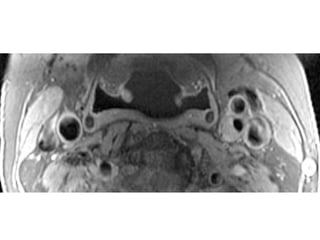

The document describes the Pathway MRITM Carotid Array coil, which is designed for high resolution imaging of small soft tissue structures like the carotid arteries. It provides images showing atherosclerotic plaque buildup in the carotid arteries, including plaque in the common carotid artery, carotid bifurcation, and internal carotid artery stenosis and plaque.